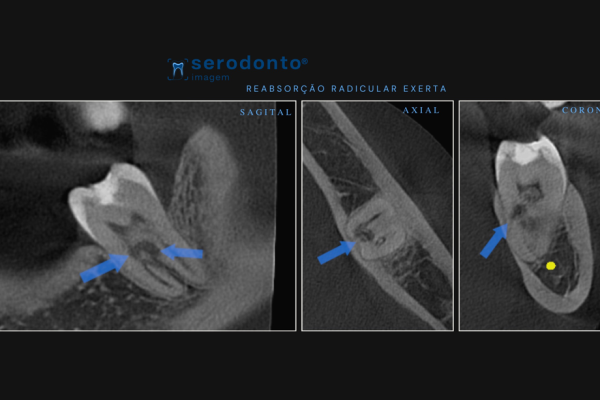

A tomografia de feixe cônico (Cone Beam) oferece imagens tridimensionais detalhadas, essenciais para diagnósticos precisos.